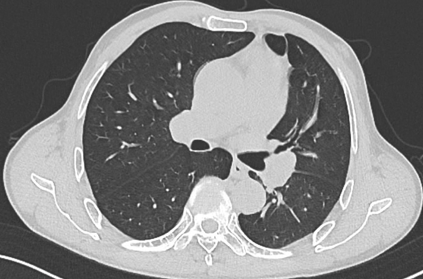

PET-CT(2023年9月):右下肺叶发现6.9×6.7×6.6cm的FDG高摄取肿块,伴右侧第7、8肋骨侵犯可疑,右肺门淋巴结肿大,双肺上叶多发结节,考虑腺癌谱系疾病。

CT及PET-CT随访(2023年11月、2024年1月):评估新辅助治疗效果,右下肺叶肿块缩小,右肺门淋巴结代谢活性消失,右肺上叶结节稳定但代谢活性降低,左肺上叶及双侧磨玻璃样病变稳定。